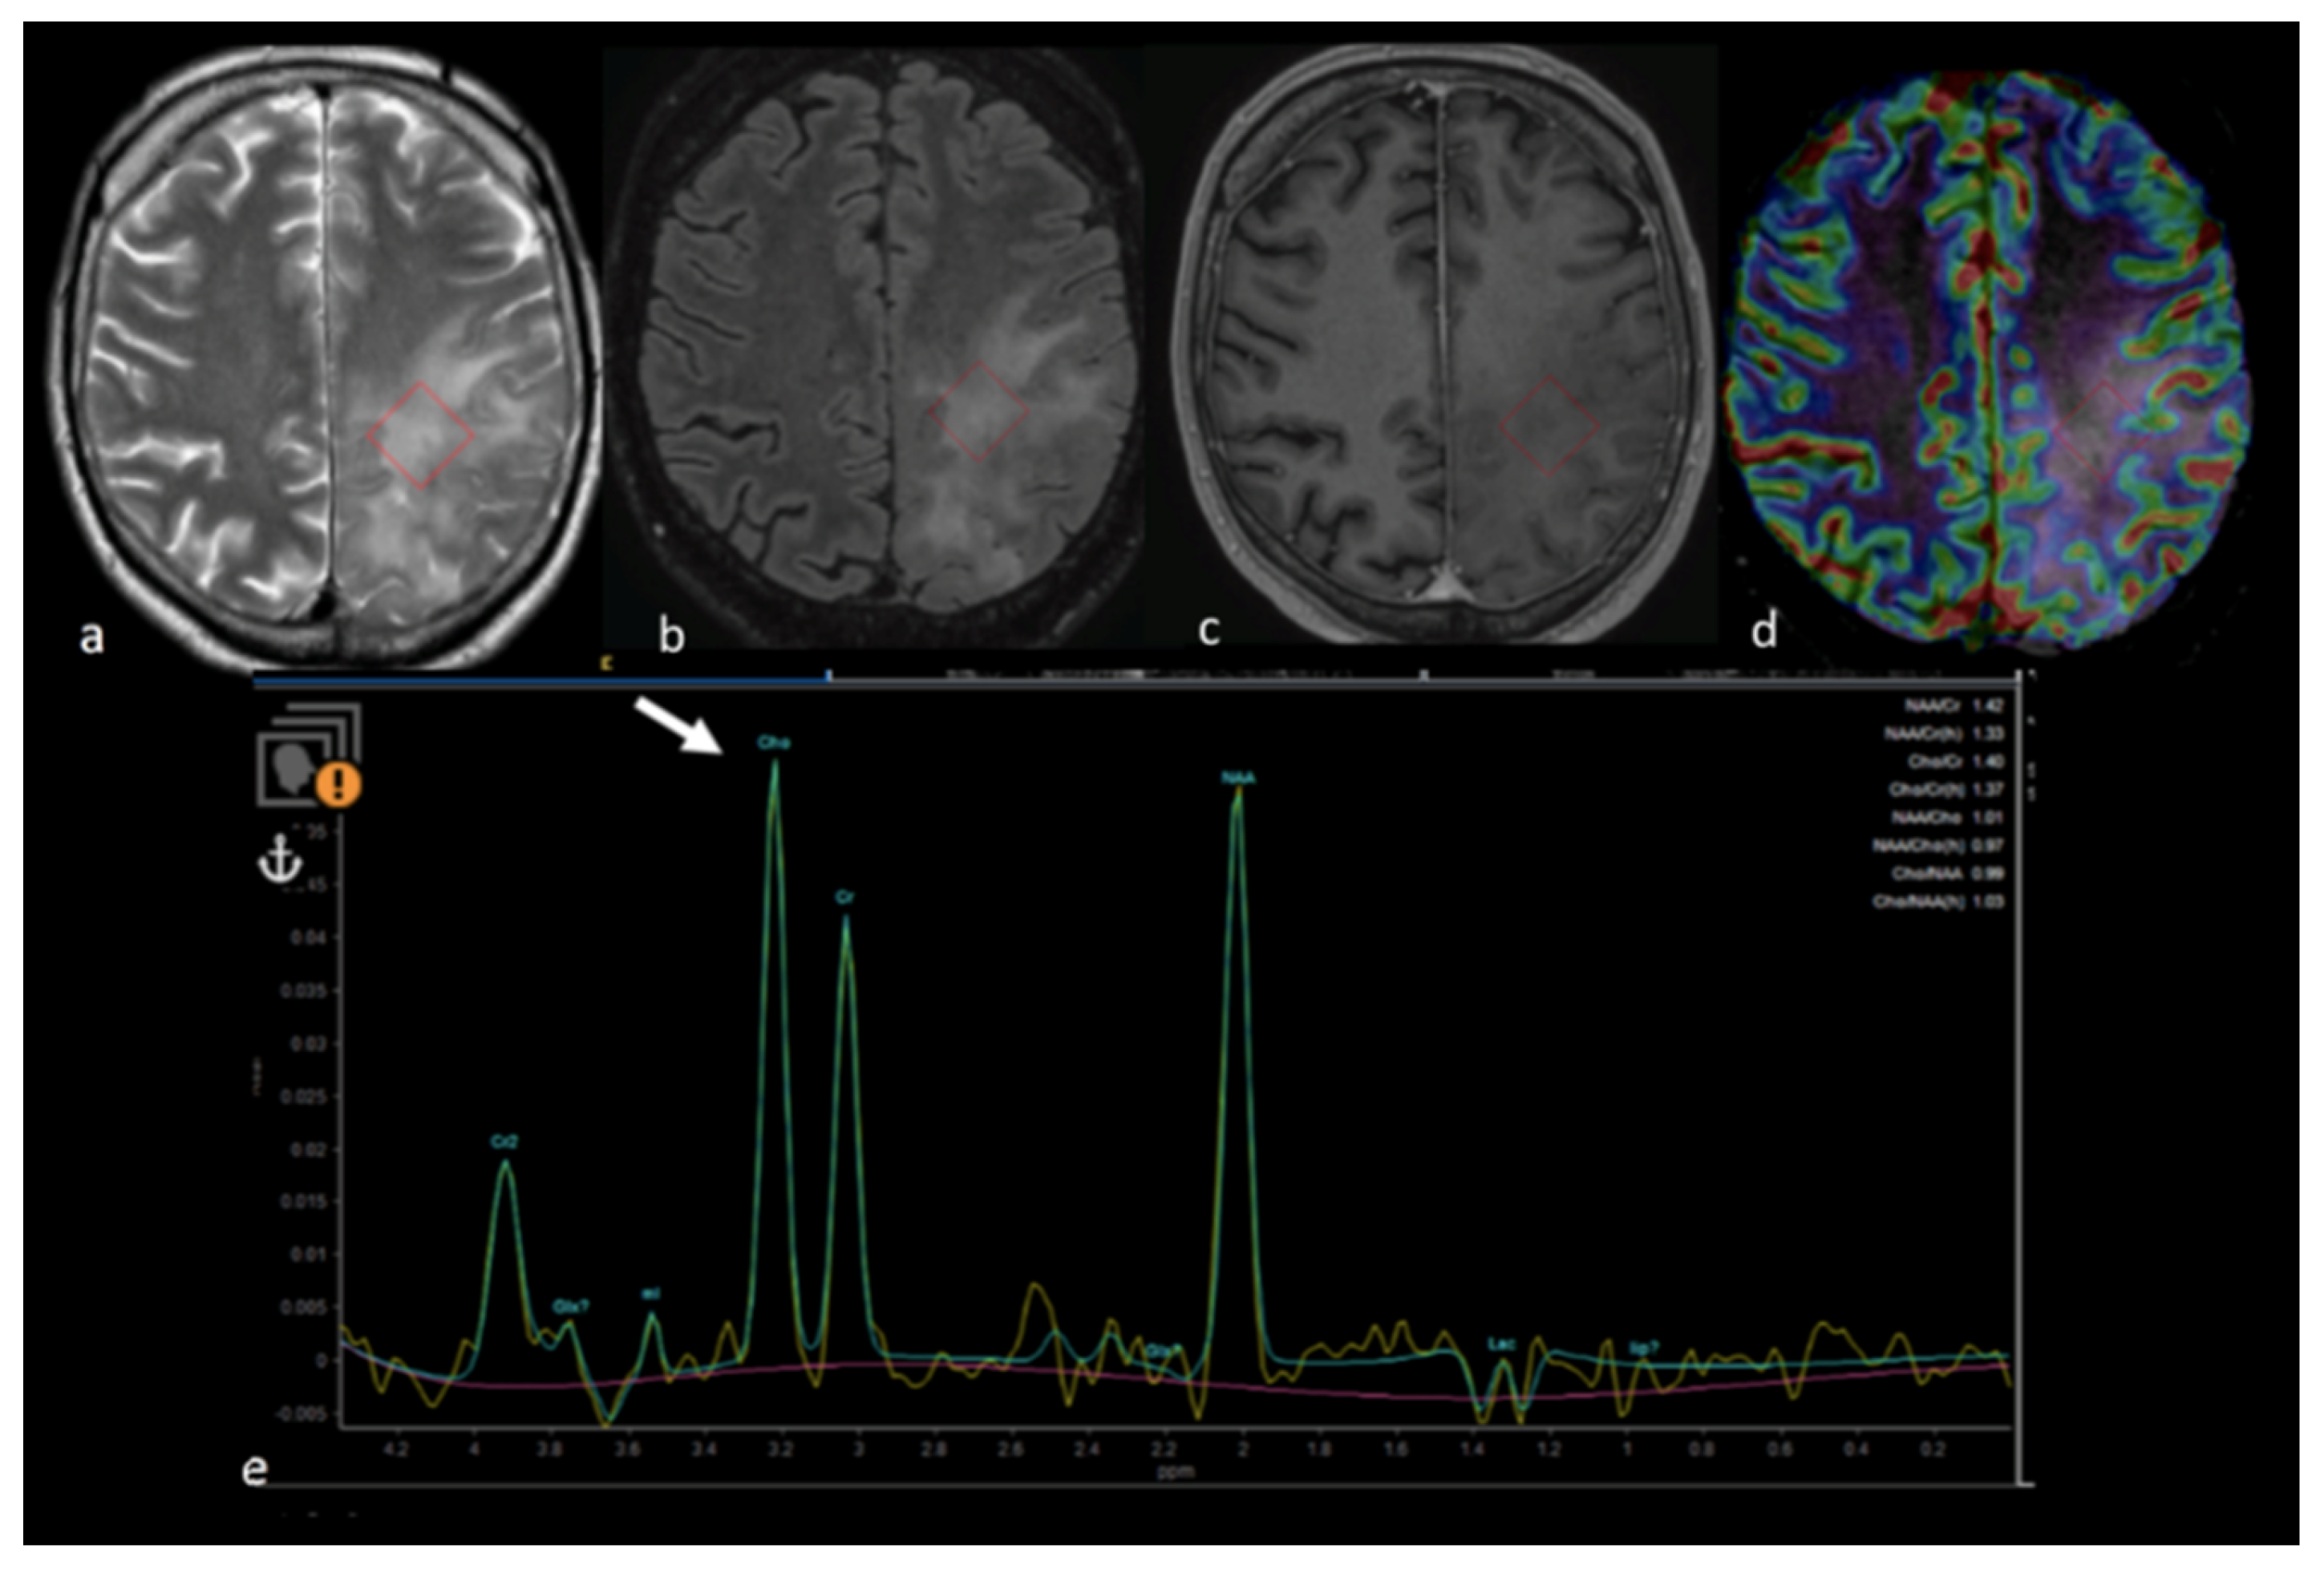

- Wijnen, J.P.; Idema, A.J.; Stawicki, M.; Lagemaat, M.W.; Wesseling, P.; Wright, A.J.; Scheenen, T.W.; Heerschap, A. Quantitative short echo time 1H MRSI of the peripheral edematous region of human brain tumors in the differentiation between glioblastoma, metastasis, and meningioma. J. Magn. Reson. Imaging 2012, 36, 1072–1082. [Google Scholar] [CrossRef] [PubMed]

- Ricci, R.; Bacci, A.; Tugnoli, V.; Battaglia, S.; Maffei, M.; Agati, R.; Leonardi, M. Metabolic findings on 3T 1H-MR spectroscopy in peritumoral brain edema. AJNR Am. J. Neuroradiol. 2007, 28, 1287–1291. [Google Scholar] [CrossRef]